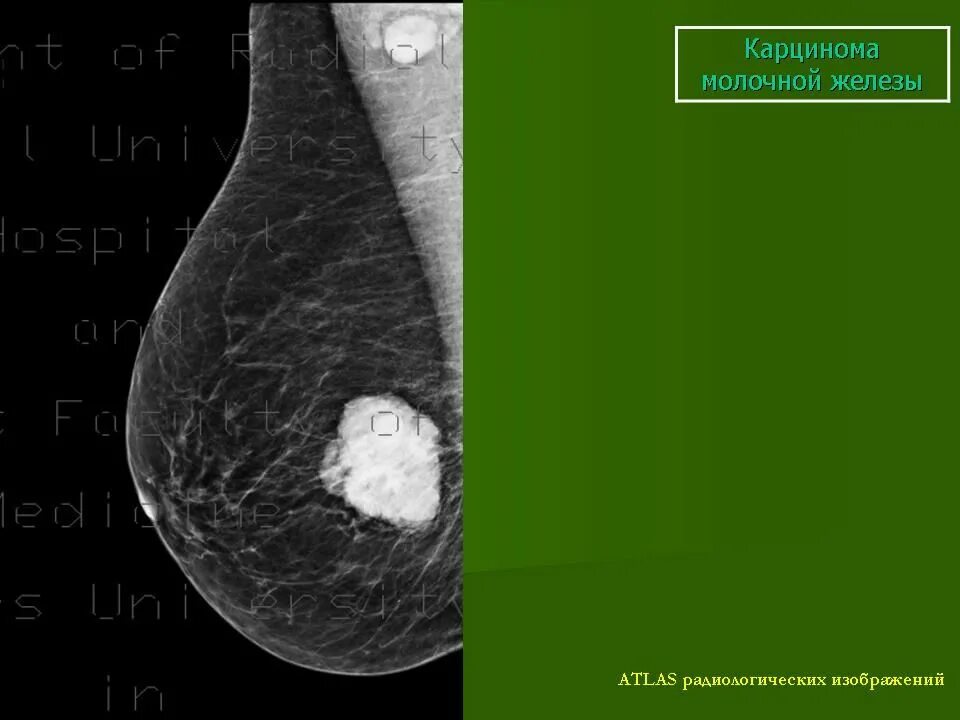

Метастазы в молочную железу